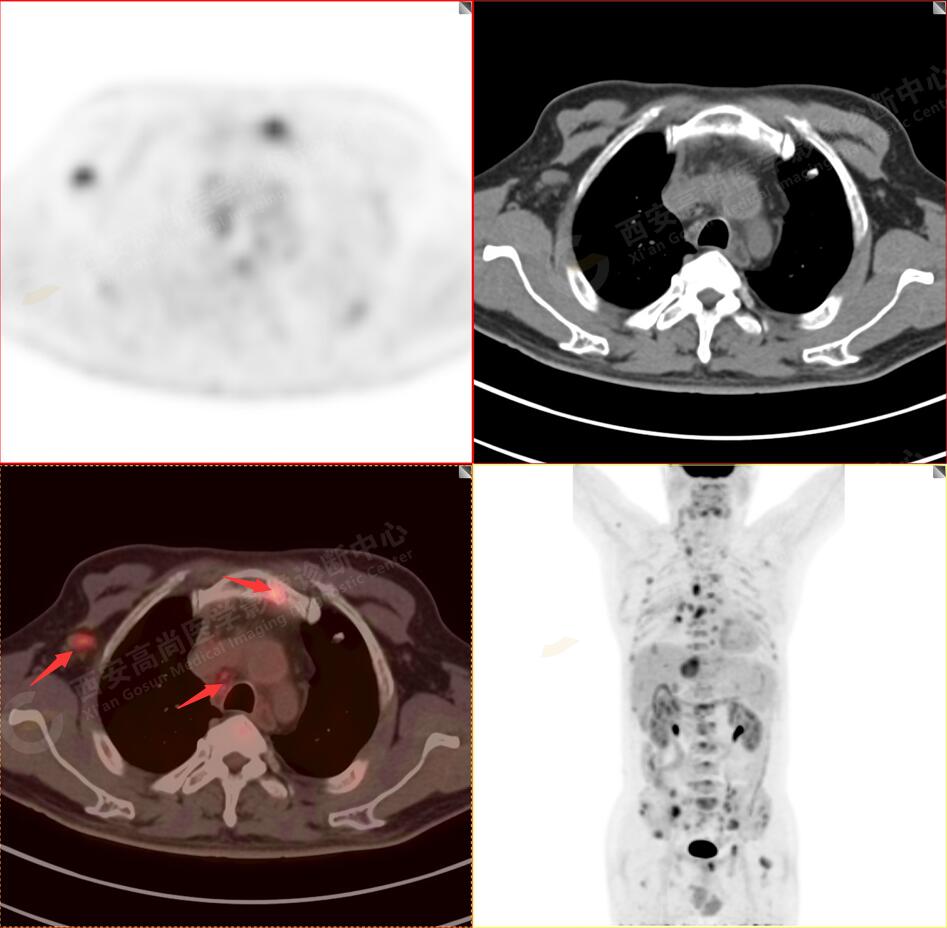

2.以下為全身多發(fā)轉移灶

3.右側頸部(Ⅱ-Ⅴ區(qū))、右側腋窩區(qū)、右側肺門及縱隔(1R、1L、2、4、6、7組)、肝門區(qū)多發(fā)腫大淋巴結,呈不同程度異常增高,均考慮為淋巴結轉移。

5.右側肱骨上段、左側肩胛骨、右側鎖骨胸骨端、胸骨、雙側多發(fā)肋骨、脊柱多發(fā)椎體及附件、雙側髂骨、雙側髖臼、雙側恥骨、雙側肱骨上段多發(fā)成骨性病變,呈不同程度FDG代謝異常增高,考慮為多發(fā)骨轉移瘤。